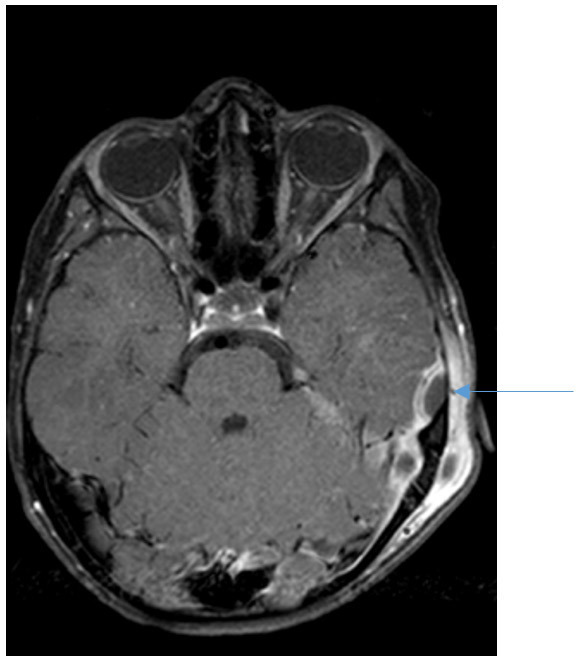

Voici le scanner injecté que vous faites réaliser

Question 7 : Quel est votre diagnostic ?

Les deux premières coupes sont des coupes frontales ou coronales ; la première en fenêtre parenchymateuse avec visualisation d’un abcès cloisonné sous-périosté, la deuxième en fenêtre osseuse avec lyse osseuse (c’est ce qui signe la mastoïdite, un comblement simple mastoïdien est présent dans les TOUTES LES OMA). Les deux dernières coupes sont des coupes axiales, l’une en parenchymateux, l’autre en fenêtre osseuse.

On voit ici sur la flèche de droite la thrombose du sinus latéral.

C’est donc une mastoïdite aiguë compliquée car s’y associe la thrombose.

L’abcès est bien ici sous-périosté à l’extérieur et au contact de l’os. Un abcès intra-parenchymateux serait en cocarde et dans la substance blanche cérébrale.